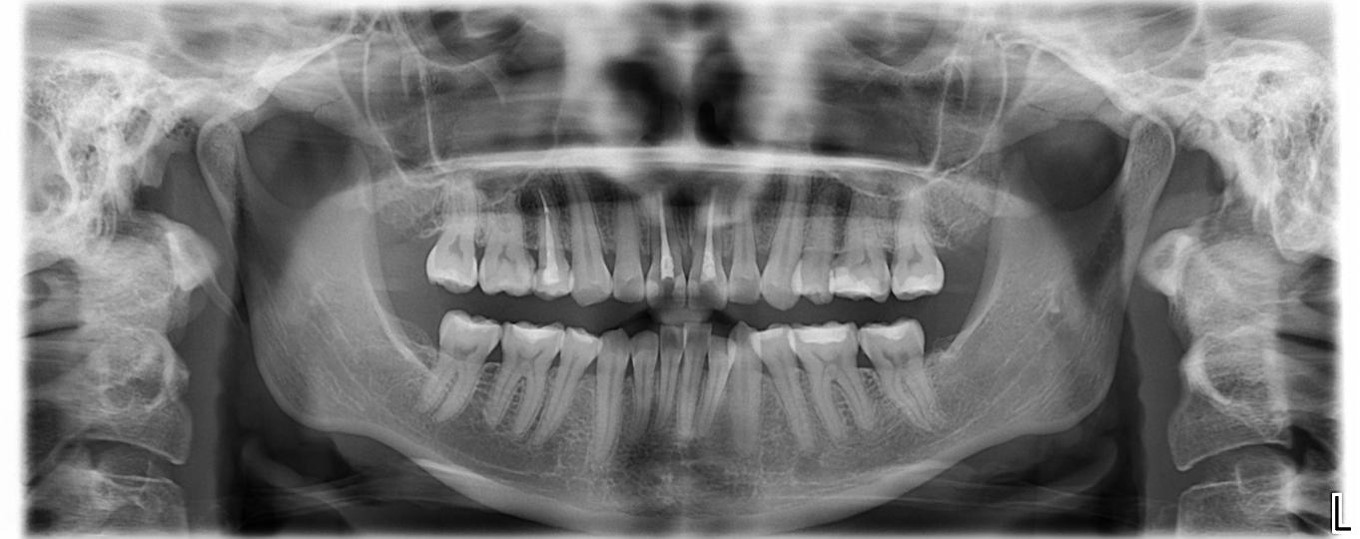

治療前,顎關節顎骨大小正常

治療前,上顎門牙已根管治療,無症狀